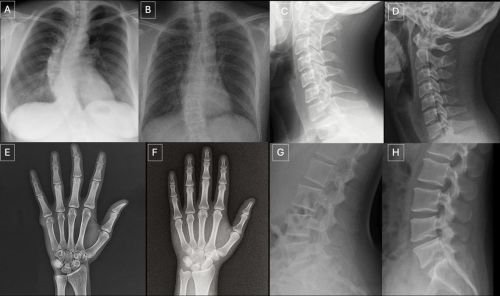

解剖结构匹配的真实X光片和GPT-4o生成的X光片:(A)真实胸部正位X光片,(B)GPT-4o生成的胸部正位X光片;(C)真实颈椎侧位X光片,(D)GPT-4o生成的颈椎侧位X光片;(E)真实手部正位X光片,(F)GPT-4o生成的手部正位X光片;(G)真实腰椎侧位X光片,(H)GPT-4o生成的腰椎侧位X光片。这些图像对比表明,GPT-4o能够在不同的解剖区域生成符合X光片特征的图像。图片来源:北美放射学会(RSNA)